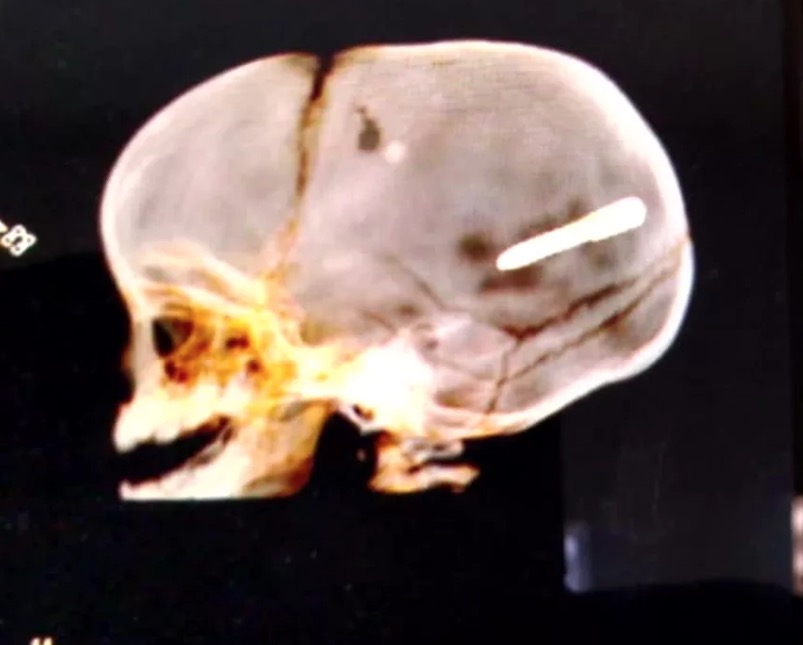

Ao perceber o buraco, olhou para Wallace e percebeu que ele estava sangrando. A mãe correu para o hospital e após a realização de uma radiografia, descobriu que o prego está alojado no crânio do bebê.

De acordo com os médicos, o estado dele é grave. Familiares foram até a construção, mas não encontraram ninguém no local.